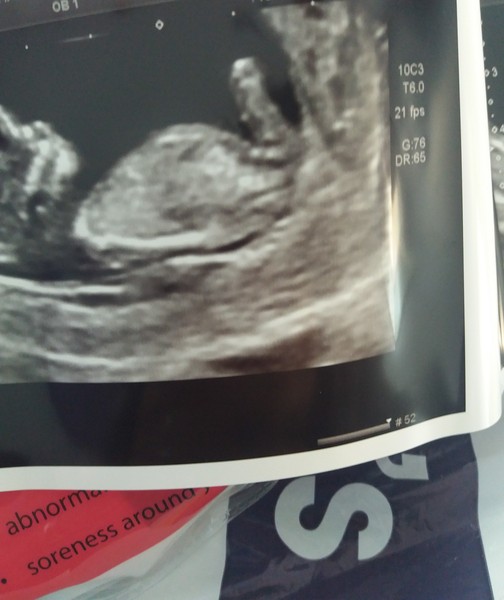

Hey everyone. Just home now. I'm shocked to say that Sticky Bean has a strong heartbeat and is all good! Can't believe it, just goes to show that you can have a little one brewing in there and feel fine and have virtually no symptoms!

Athers666 · 06/06/2018 12:28

Here's Little Dude.

Athers that’s wonderful news. What a gorgeous little bubba. Dude? Is it a boy? X

That's such a great pic Athers666!!!